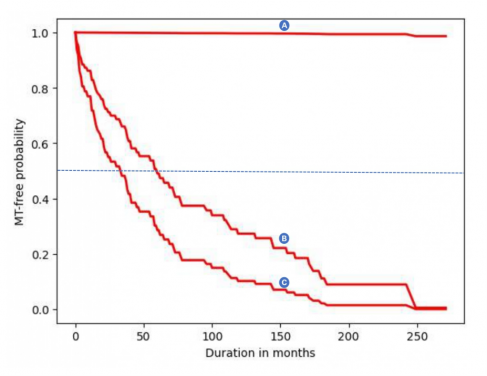

(Figure 1) The curve can be used by doctors and dentists to compare the risk levels of two or more OL/OLM patients. Generally, an increasingly lower likelihood of developing cancer is expected for the duration where the risk probabilities range from 0.5 (the dashed blue line) to 1.0. In the graph, the predicted cancer risk level for patient A is lower than patients B and C. Patient C has the highest risk of cancer occurrence and will require very close monitoring following cancer-preventive surgery.

To expatiate on how the interactive web tool functions, it requires 26 pieces of information on the demography, clinical and pathological description of the disease, and treatment received by the OL/OLM patient. The predicted output from the web tool includes a curve from which the different risk levels (vertical axis) can be visualized at each time point (horizontal axis). These predicted risk levels have been shown to be accurate up to 17 years from the time that the information was entered.

The prediction curve may also be used for individual cancer risk estimation and inform health professionals when to commence very close monitoring of patients when a certain risk level is reached. (Figure 1)

For OL/OLM patients, risk awareness may motivate them to regularly attend routine follow-up visits and allow them to make informed decisions when providing consent for biopsy when required.

Of note, the predicted risk curve may change with varying input data such as smoking and alcohol drinking status, parts of the mouth that are affected, treatment received, lesion recurrence, and the severity of epithelial dysplasia during treatment monitoring.